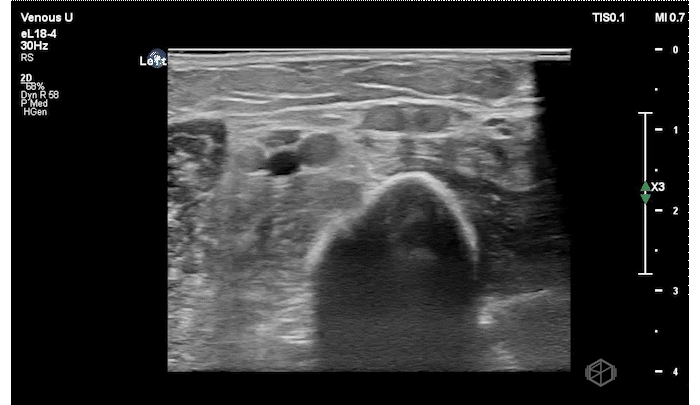

Dr. Vazquez had a 78-year-old female with a history of a recent pacemaker placement present to the ED for shortness of breath and left arm pain. The patient had a new pericardial effusion (which was the real reason for her shortness of breath) as well as the below finding in her LEFT upper extremity.

The patient has an echogenic thrombus visible in the LEFT distal subclavian vein to the branch point at the anterior cubital fossa.

Diagnosis: Left upper extremity DVT